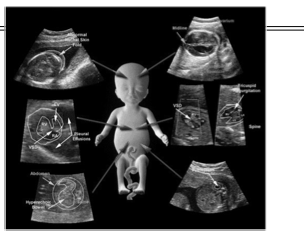

triploidy sono findings

A

IUGR

MCDK

hydro

ambiguous genitalia

CHD

omphalocele

CNS